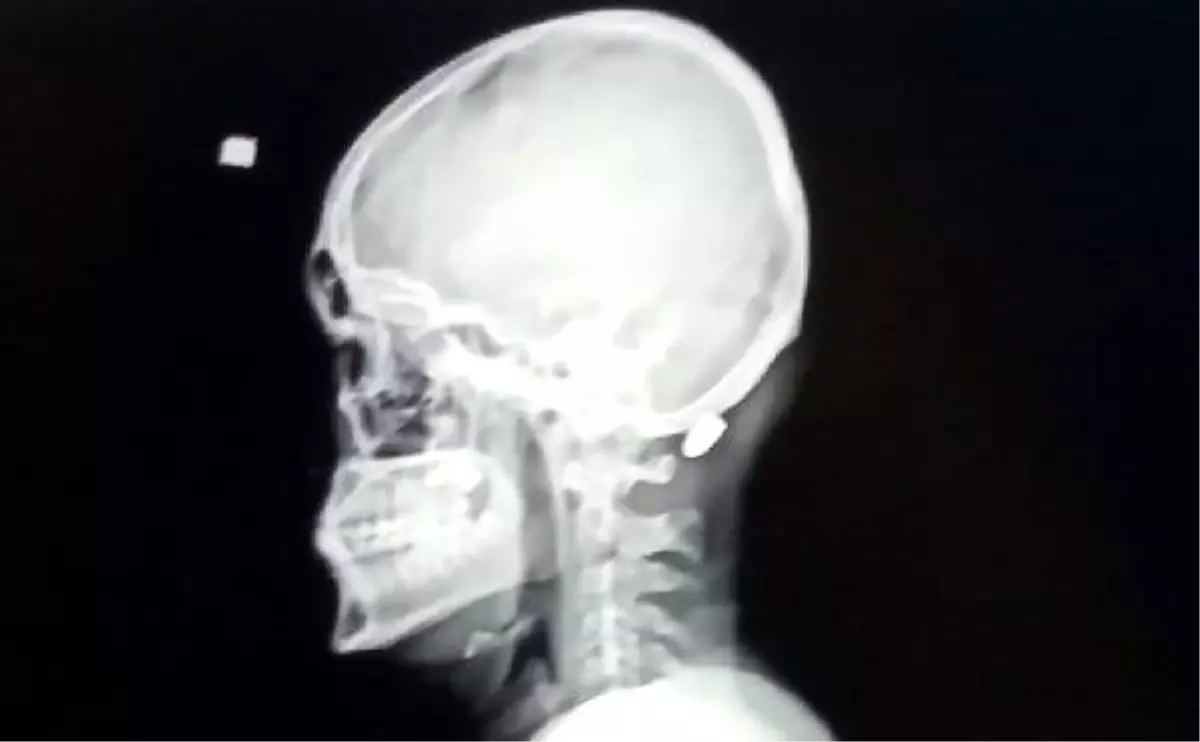

Olay, dün akşam saatlerinde Ortahisar ilçeye bağlı Tosköy Mahallesi'nde meydana geldi. Lise öğrencisi İsmail Bekar, ailesiyle birlikte evlerinin önünde otururken, bir anda kolu kanlar içerisinde kaldı. Kolunda acı hisseden Bekar, ailesi tarafından Trabzon Yavuz Selim Kemik Hastalıkları Hastanesi'ne kaldırıldı. Tedaviye alınan Bekar'ın sağ kolunun üst kısmında mermi girişi tespit edildi. Maganda kurşunu ile yaralandığı belirlenen İsmail Bekar, tedavisinin ardından taburcu edildi. Polis ve jandarma ekipleri, bölgede silahı ateşleyen kişinin belirlenip, yakalanması için çalışma başlattı.

Öte yandan Trabzon'da son 1 ay içerisinde maganda vakalarında yaşanan artış da tepkilere yol açtı. Emniyet yetkililerin yanı sıra pek çok kent sakini, sosyal medya hesaplarından paylaşımda bulunarak, istenmeyen olayların meydana gelmemesi için düğün, nişan gibi özel günlerde özellikle meskün yerlerde havaya silahla ateş açılmamasını istedi. Kentte son 20 gün içerisinde; Trabzon'un Tonya ilçesinde, yorgun merminin başına isabet etmesi sonucu ağır yaralanan Sabri Baştan (86), kaldırıldığı hastanede yapılan müdahalelere rağmen kurtarılamamıştı. Akçaabat ilçesinde evinin balkonunda oturduğu sırada maganda kurşununun karın bölgesine isabet ettiği Davut Serbest (59), ağır yaralanırken, Vakfıkebir ilçesinde yaylada gezindiği sırada magandanın hedefi olan lise öğrencisi Ali Kuleyin'in (18) ensesine isabet eden yorgun mermi, ameliyatla çıkarılmıştı. Trabzon'un Şalpazarı ilçesinde maganda kurşununun kaşına isabet ettiği Burak Yamaç (15) ise hastanede yapılan müdahalelere rağmen sağ gözünün görme yetisini kaybetmişti.